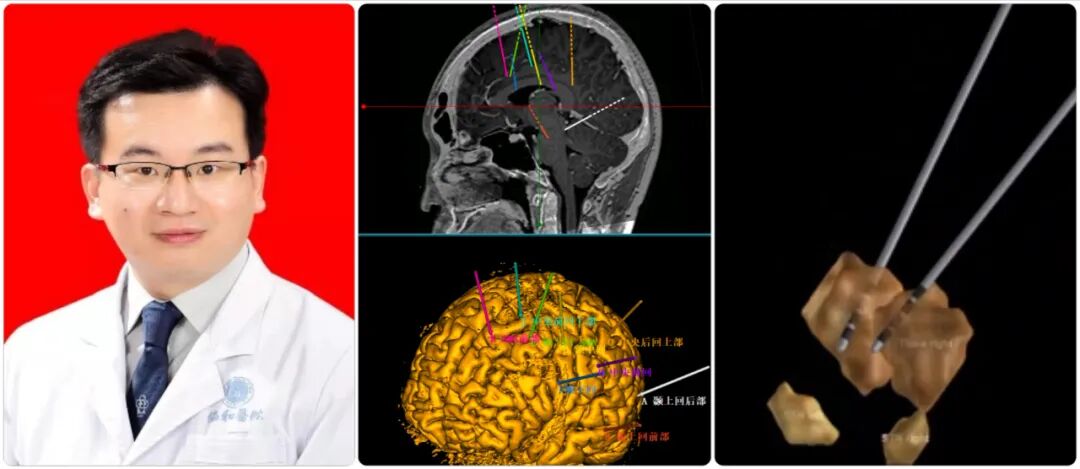

第613期-美敦力DBS特刊 | 专访301医院徐欣:可感知DBS技术  将为帕金森患者打开术后程控的“黑箱”